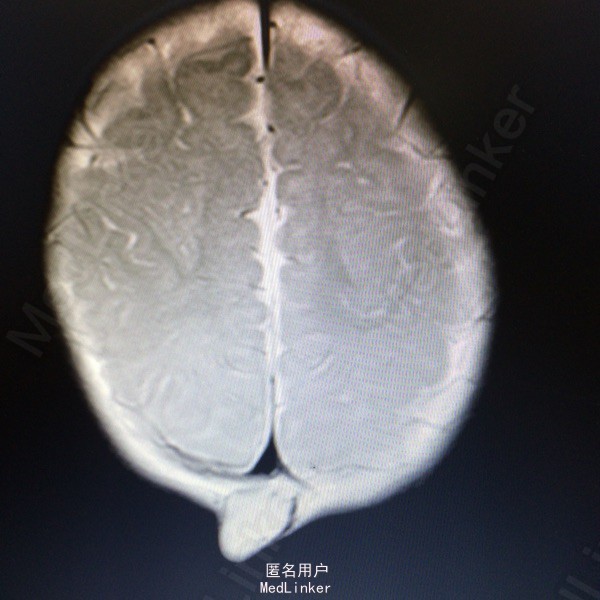

主诉:发现枕部肿块7个月 病史:患儿7月男婴,出生后即被家人发现枕后部肿物,大小约1cm*1cm*1cm,边界清楚,质软,表面光滑,挤压时患儿无哭闹等。

查体:枕后部肿物 辅助检查:行头颅MR提示顶针部中线异常信号,多考虑脑膜膨出

诊断:脑脊膜膨出 处理:枕部脑膜膨出囊切除术➕硬脑膜修补术